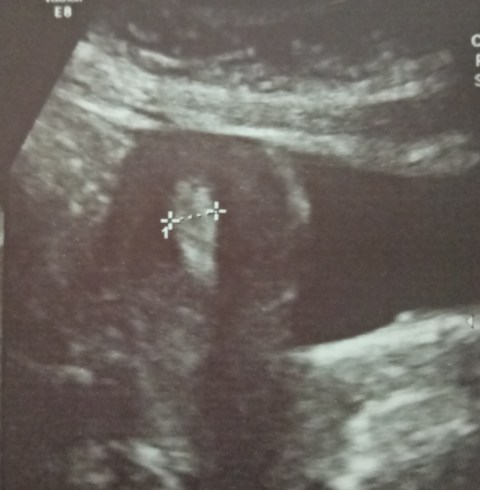

2.7.18

A big phyllodes tumor in the left breast of a young girl (18 years old) excised.